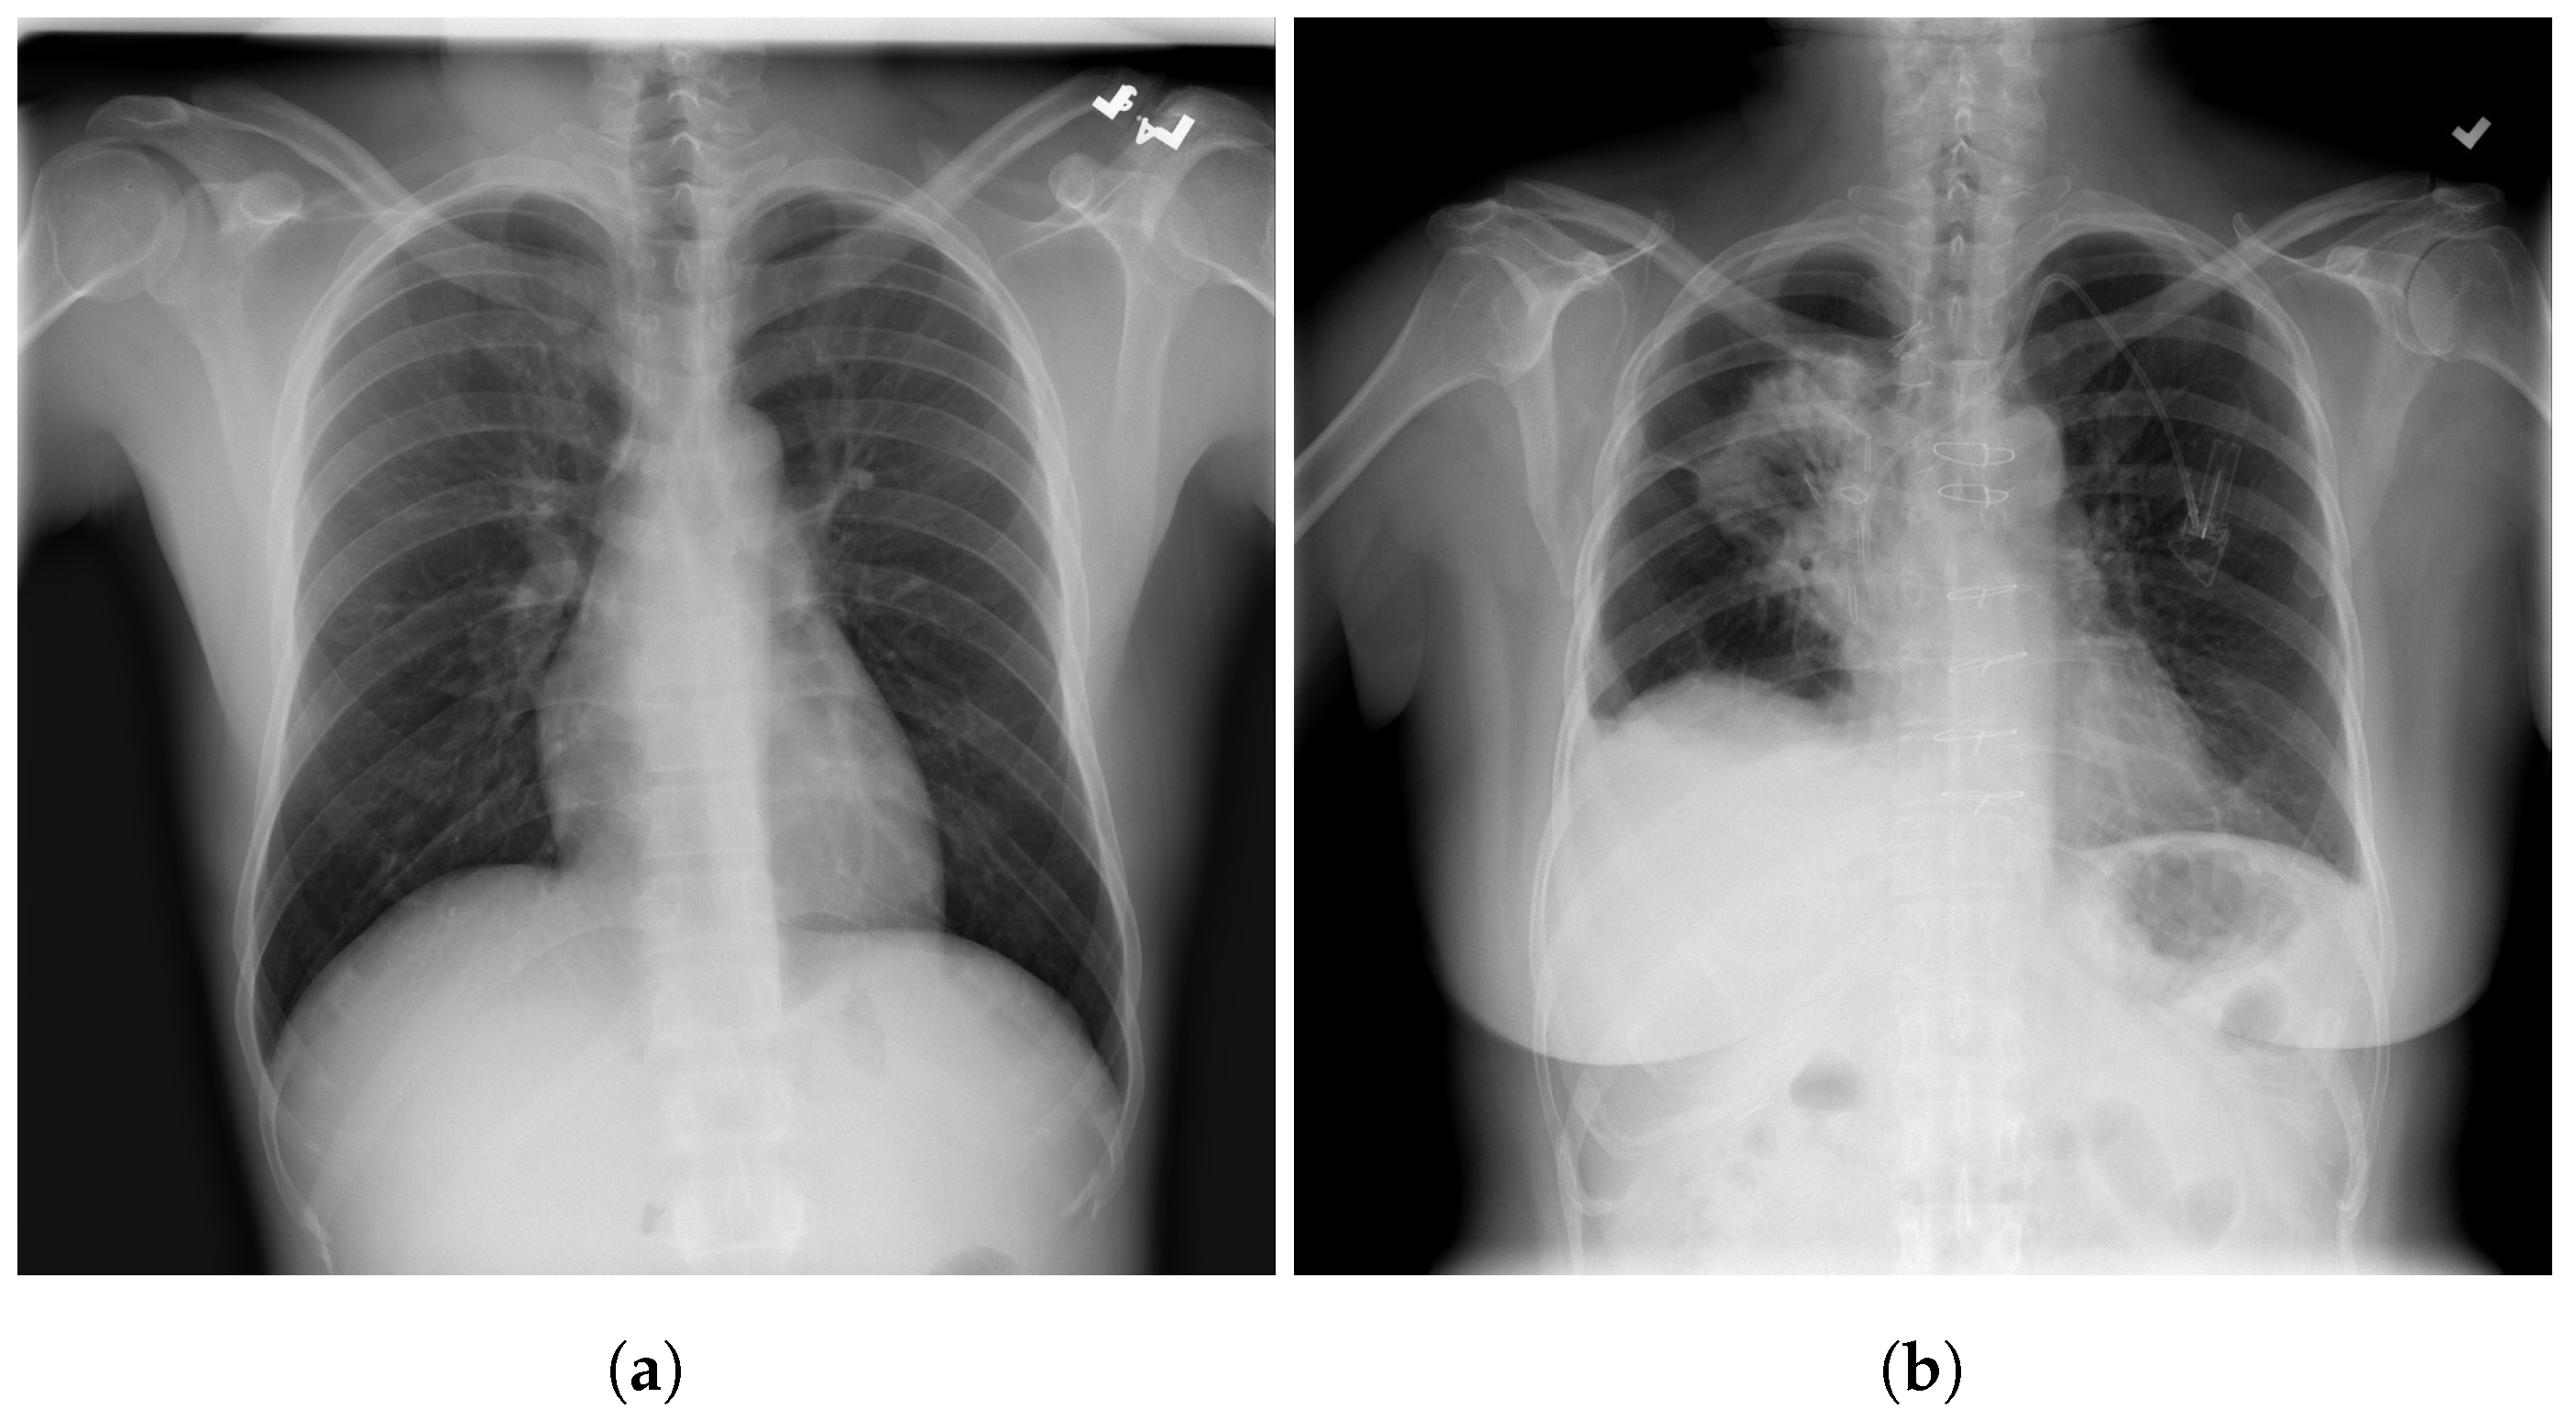

2. Proposed Approach

3. Datasets

5. Individual Tests